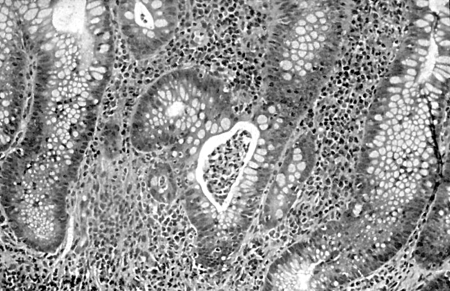

Microscopically, UC usually involves only the mucosa, with the formation of crypt abscesses and a coexisting depletion of goblet cell mucin. In severe cases, the submucosa can be involved, and in some cases, the deeper muscular layers of the colonic wall can also be affected. Further microscopic changes include inflammation of the crypts of Lieberkuhn and abscesses. Ulcerated areas are soon covered by granulation tissue. The undermining of mucosa and the excesses of granulation tissue form polypoidal mucosal excrescences, known as inflammatory polyps or pseudopolyps.[1][2][3][18][19][Figure caption and citation for the preceding image starts]: Colonic biopsy specimen showing severe mucosal inflammation, formation of crypt abscess, mild glandular atrophy, and distortion, suggesting an active phase of ulcerative colitis; haematoxylin/eosin staining, ×400 magnificationFrom Iannone F, Scioscia C, Musio A, et al Leucocytoclastic vasculitis as onset symptom of ulcerative colitis Ann Rheum Dis 2003 Aug;62(8):785-6; used with permission [Citation ends].